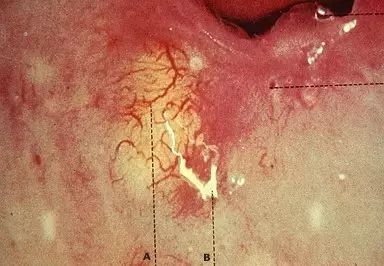

巴氏腺囊肿及脓肿

25%~50%患者感染初期无症状,主要症状是阴道分泌物增多及外阴瘙痒,间